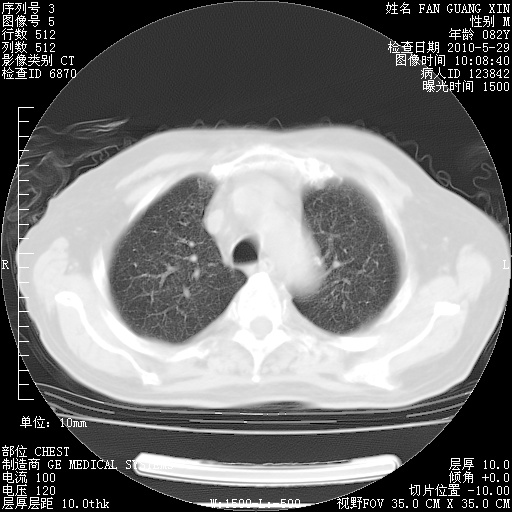

再治疗10天后的肺部CT

阅读此次胸部CT,肺间质渗出性改变较入院时有吸收。目前从体温、白细胞、中性分叶明显增高,肯定存在细菌感染(发生医院感染哦,若无消化道及泌尿系统等感染的依据,肺部感染可能大)。若你院头孢哌酮舒巴坦钠耐药率较高,同意你的方案,若48小时体温仍高,可考虑使用碳青霉稀类抗菌药物,同时可予超声雾化、注意滴数时加大液体量。白蛋白33.30g/L较低哦,需加强营养等支持治疗。